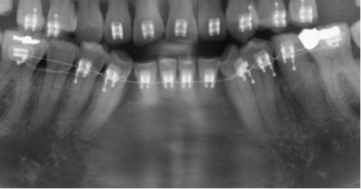

Los resultados mostraron que en el 48 % de la población se encontró algún hallazgo relacionado con la pulpa dental, con frecuencias similares entre hombres y mujeres, siendo el tratamiento endodóntico el más frecuentemente encontrado (Tabla 1, Fig. 1). El rango del número de endodoncias por radiografía fue de 1 a 18. El 86,4 % de las radiografías presentaron de 1-5 endodoncias, 11,4 % de 6-10 y el 2,2 % de 11-18. La presencia de zona radiolúcida periapical seguida por la reabsorción (Fig. 2), fueron los siguientes hallazgos más frecuentes. (Tabla 1)

El análisis de la presencia de zona radiolúcida periapical, mostró que del total de dientes en boca, el 0,6 % de los que no tenían endodoncia tienen lesiones apicales mientras que el 11% de los que tienen endodoncia se asocian con una lesión apical (p<0,000000). Sin embargo el cálculo del OR (OR=0,047) mostró una relación negativa de riesgo entre tener una endodoncia y presentar lesión apical. De los 389 dientes en los que se observó el hallazgo compatible con radiolucidez periapical, 171 (44 %) tenían tratamiento endodóntico, de los cuales 66 % estaban subobturados, 31% bien obturados y 3% sobreobturados.

Un hallazgo importante en este estudio fue encontrar que el 52,7 % de los dientes se consideraron subobturados, asociados en un 66% con lesiones apicales vs el 44.9 % en aquellos que estaban en límites de normalidad. Esto coincidiendo con De Moor y colaboradores 11 que encuentran que del 6,8 % de dientes que están obturados, el 56,6 % fueron considerados mal obturados. Un análisis utilizando tomografía de rayo de cono, mostró que el 23,04 % de dientes están mal obturados y en ellos el riesgo de tener una lesión apical aumenta en 4,38 veces17. Un estudio de Moreno y colaboradores18 mostró que el 51% de los dientes tratados, no presentaban patologías perirradiculares y solo el 33% se consideraron correctamente obturados.